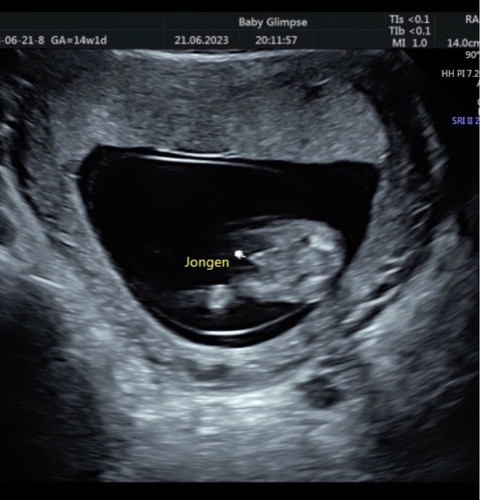

Ik twijfel nog omdat het bij mijn kindje iets uitsteekt met 18 weken maar wel 3 strepen heeft. Maar niks zien bij jongen is bijna onmogelijk, bijna!

Bedankt voor je reactie :) Dan kan ik beginnen met shoppen 💗💗 Hebben ze bij jou op 18 weken nog niet kunnen bevestigen wat het geslacht is? of is hetgeen wat uitsteekt de reden waarom je twijfelt? :)